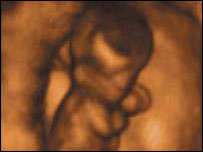

دایاں یا بایاں: پیدائش سے پہلے

ہاتھوں کے استعمال کا رجحان پیدائش سے پہلے شروع ہوجاتا ہے

ماں کے پیٹ میں دس ہفتے کے بچے میں جس ہاتھ کو استعمال کرنے کا رجحان ہوگا وہی ہاتھ وہ ساری عمر استعمال کرے گا۔